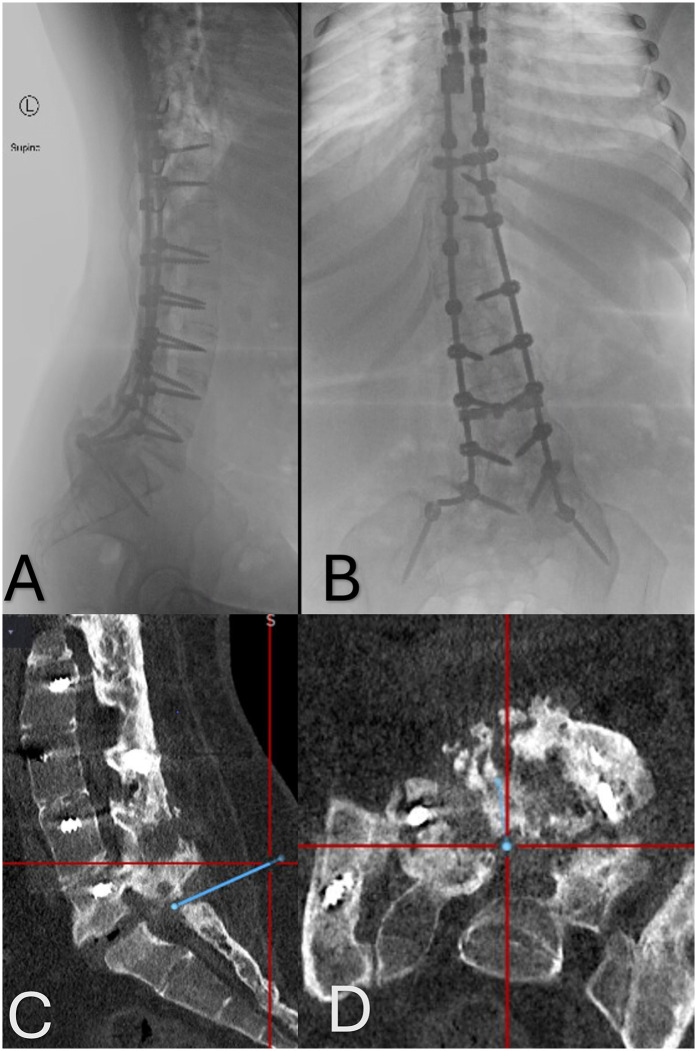

Case report:  We present the case of a 27-year-old female with T2 American Spinal Injury Association (ASIA) A spinal cord injury (SCI) and chronic spastic dystonia. She was maximized on oral medications without satisfactory control of her painful muscle spasms and was a candidate for ITB trial, which ultimately failed due to the difficulty of accessing the spinal canal due to extensive pseudoarthrosis secondary to thoracic to lumbar fusion. A decision was made to directly implant the pump in the operative room using O-arm-aided neuronavigation to guide catheter access at L5-S1. Currently, at 22 months of follow-up post-pump implant, ITB delivery has led to persistent improvements in her spastic dystonia and many aspects of quality of life.